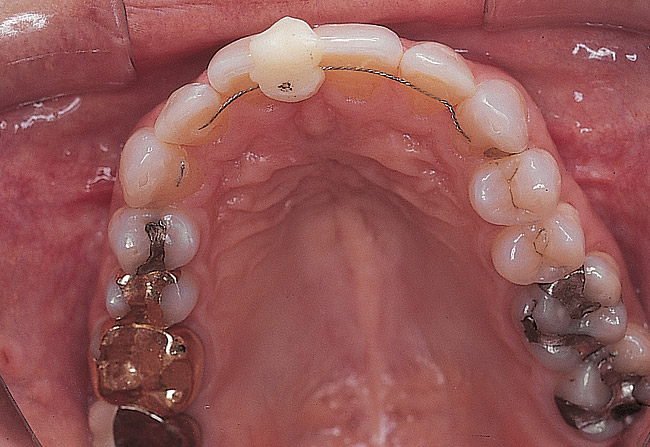

Figure 2  Preoperative maxillary occlusal view.

Figure 2